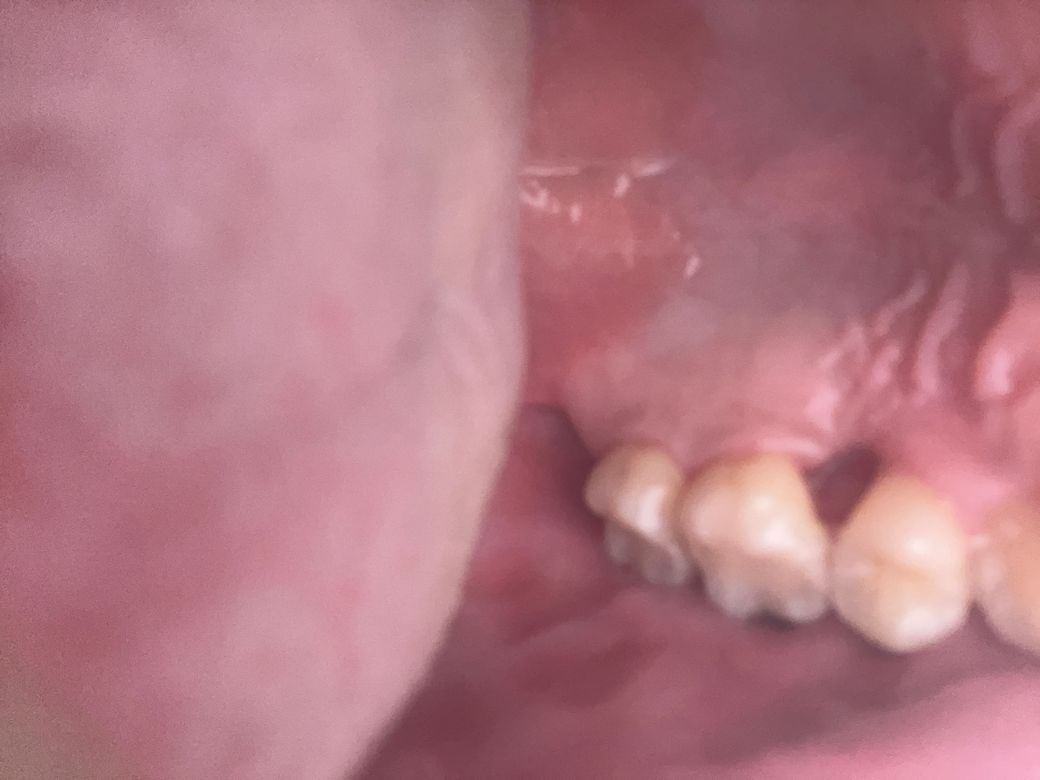

매복과잉치 발치후 구멍 방법없을까요?

교정중 매복과잉치 발치 수술후 구멍이 크게나있는데

매꿔지지않는다고합니다 뼈이식을해도 구멍은 사라지지않을꺼라 하던데 방법없을까요..

• 1번 째 사진

발치한 지 얼마나 경과 하였는지 질문에 나와있지는 않지만 저 정도면 시간이 지나면 점점 잇몸살이 차 올라와 구멍이 없어질 것으로 보입니다. 저건 경우에 뼈이식을 할 필요는 없습니다.

현재 어떠한 상태에서 발치를 했는지에 따라서 잇몸 라인이 어느정도 회복될지 다를 수 있습니다. 사진 자체만으로는 알 수 없으나 정상적인 발치라면 잇몸은 회복됩니다. 하지만 병적으로 치조골이 이미 내려간 경우라면 더 이상 올라오지 않습니다.